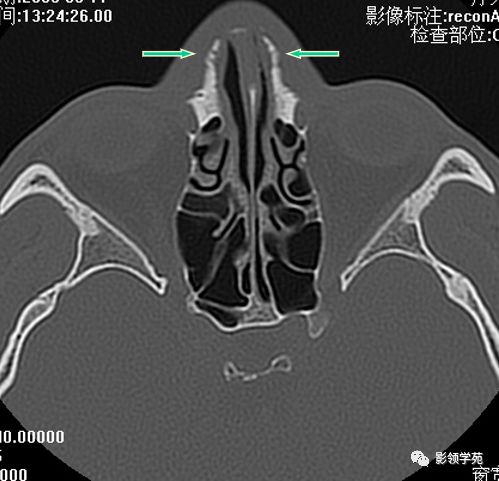

双侧鼻骨骨折

双侧上颌骨额突骨折